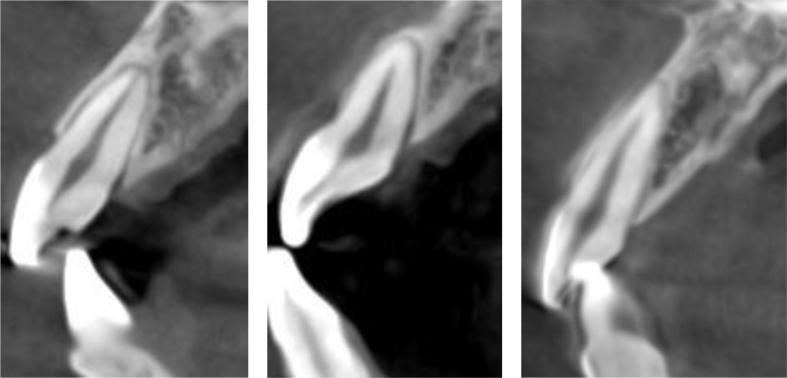

The patients were divided by smoking, gender, age, and root sagittal position in the alveolar bone. BBW thickness was measured at the following sites: the 4 mm apical to the CEJ, the middle of the root, and the apex. The distance from the CEJ to the FBC was also evaluated.

Cone beam CT (CBCT) data for the maxillary central incisors of 645 patients (323 males and 322 females) were selected and analyzed. The CEJ-FBC distance in patients who smoked (2.79 ± 0.78 mm) was significantly greater than that of non-smokers (2.54 ± 0.69 mm). The BBW in subtype III (0.74 ± 0.43 mm, 0.81 ± 0.36 mm) was thinner than that in subtypes I and II at 4 mm apical to the CEJ and in the middle of the root, with a statistically significant difference ( < 0.05).

患者按吸烟情况、性别、年龄以及牙槽骨中牙根矢状位进行分组。在以下部位测量BBW厚度:CEJ根尖4mm处、牙根中部和根尖。还评估了从CEJ到FBC的距离。

选取并分析了645例患者(323例男性和322例女性)上颌中切牙的锥形束CT(CBCT)数据。吸烟患者的CEJ-FBC距离(2.79±0.78mm)显著大于不吸烟患者(2.54±0.69mm)。在CEJ根尖4mm处和牙根中部,III型亚型的BBW(0.74±0.43mm,0.81±0.36mm)比I型和II型亚型更薄,差异有统计学意义(<0.05)。